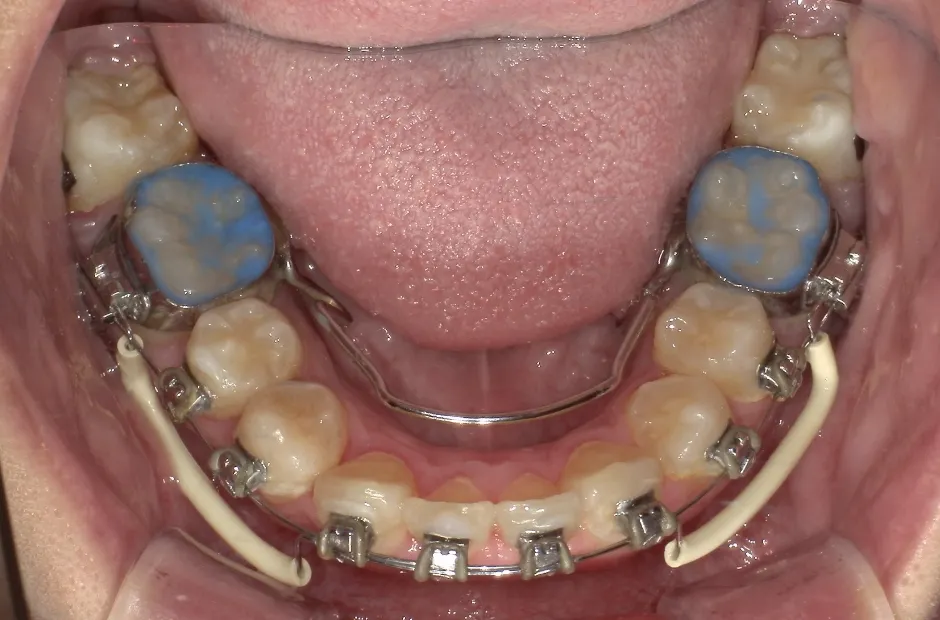

開咬

| 診断名・主訴 | 開咬 |

|---|---|

| 年齢・性別 | 18歳・男性 |

| 治療期間・回数 | 1年 12回 |

| 治療に用いた主な装置 | ロール付きリンガルアーチ |

| 抜歯部位 | なし |

| 治療費 | 70万円(税抜) |

| リスク・副作用 | 装置による違和感・疼痛・歯肉退縮・歯根吸収・虫歯のリスクなど |

治療中